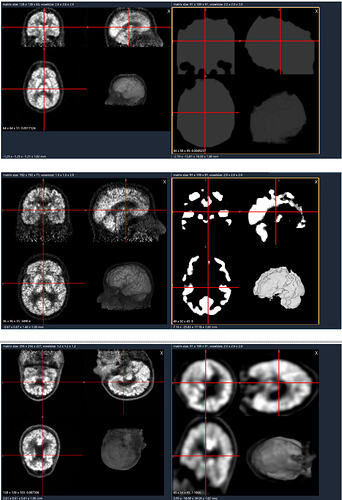

I’m new to neurodata and I am learn to preprocess 18F-FDG Pet images for deep learning models. Raw data (left one) n output (right one) look like this:

But after preprocessing (spatial norm using MNI template + intensity normalization + gaussian smoothing), they are all look wrong, can you tell me help me identify what is the problem with my matlab code, and should i use spm matlab for preprocessing PET data or is there any robust python toolbox for preprocessing PET data, here is my code. Thank you so much for your help.